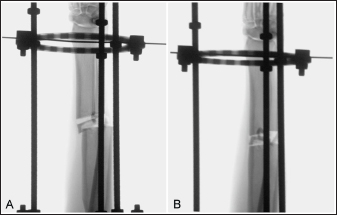

The total procedure time as well as incremental times for the subcategories of fixator placement, reduction, radial approach, and plate application did not differ between the cranial and medial plating groups (Table 1). Placement of the proximal Kirschner wire was more cumbersome than distal wire placement in both plating groups. Proximal cranial-to-caudal Kirschner wire placement was also more challenging than medial-to-lateral wire placement. Wire obliquity had to be addressed in four limbs in the cranial plating group and five limbs in the medial plating group. Obliquity was addressed by placing flat washers on one or both of the fixation bolts securing the Kirschner wire (n=1 limb in each plating group), attaching the fixation wire on opposite surfaces of the ring (n=1 and 2 in the cranial and medial plating group, respectively), or removing and replacing the wire (n=4 and 3 in the cranial and medial plating group, respectively). Lateral translation of the distal fracture segment along the Kirschner wire was performed to improve frontal plane alignment prior to plating in three limbs in the cranial plating group (Fig. 2). Caudal translation of the distal fracture segment along the Kirschner wire was performed to improve sagittal plane alignment prior to plating in two limbs in the medial plating group (Fig. 3). Obtaining sufficient exposure of the proximal radius to allow for plating required substantial tissue dissection, particularly in larger cadavers in both plating groups. The distal ring interfered with establishing a distal-to-proximal epiperiosteal tunnel in one limb in the cranial plating group, necessitating proximal-to-distal development. Plate orientation was more craniomedial than medial in six limbs in the medial plating group. Bone-holding forceps were used to improve reduction and alignment and to maintain appropriate plate position on the radius during plating in five limbs in the cranial plating group and six limbs in the medial plating group. Alignment was also similarly improved using bone holding forceps following initial plate placement by loosening then retightening or removing and replacing screws in four limbs in both plating groups (Fig. 4). The proximal or distal ring interfered with inserting the locking drill guide into the plate in three limbs in both plating groups. The fixator was removed in these limbs to allow placement of the final proximal or distal screw. Total and incremental procedure subcategory Likert scores assessing ease of performance did not differ between plating groups (Table 2). The number of fluoroscopic images (mean ± SEM: 8.7 ± 0.9 and 9.0 ± 0.8 for cranial and medial plating groups, respectively) obtained during the procedure did not differ between plating groups (p =0.77).

Fig. 4. Fluoroscopic images of a limb assigned to the cranial plating group. After initial plating, there was valgus angulation of the distal fracture segment (A). The two most-proximal screws engaging the distal radial segment were removed and the distal screw was loosened and bone-holding forceps were applied through the plate insertional incision to improve alignment (B). Screws were subsequently reinserted and the distal screw tightened.